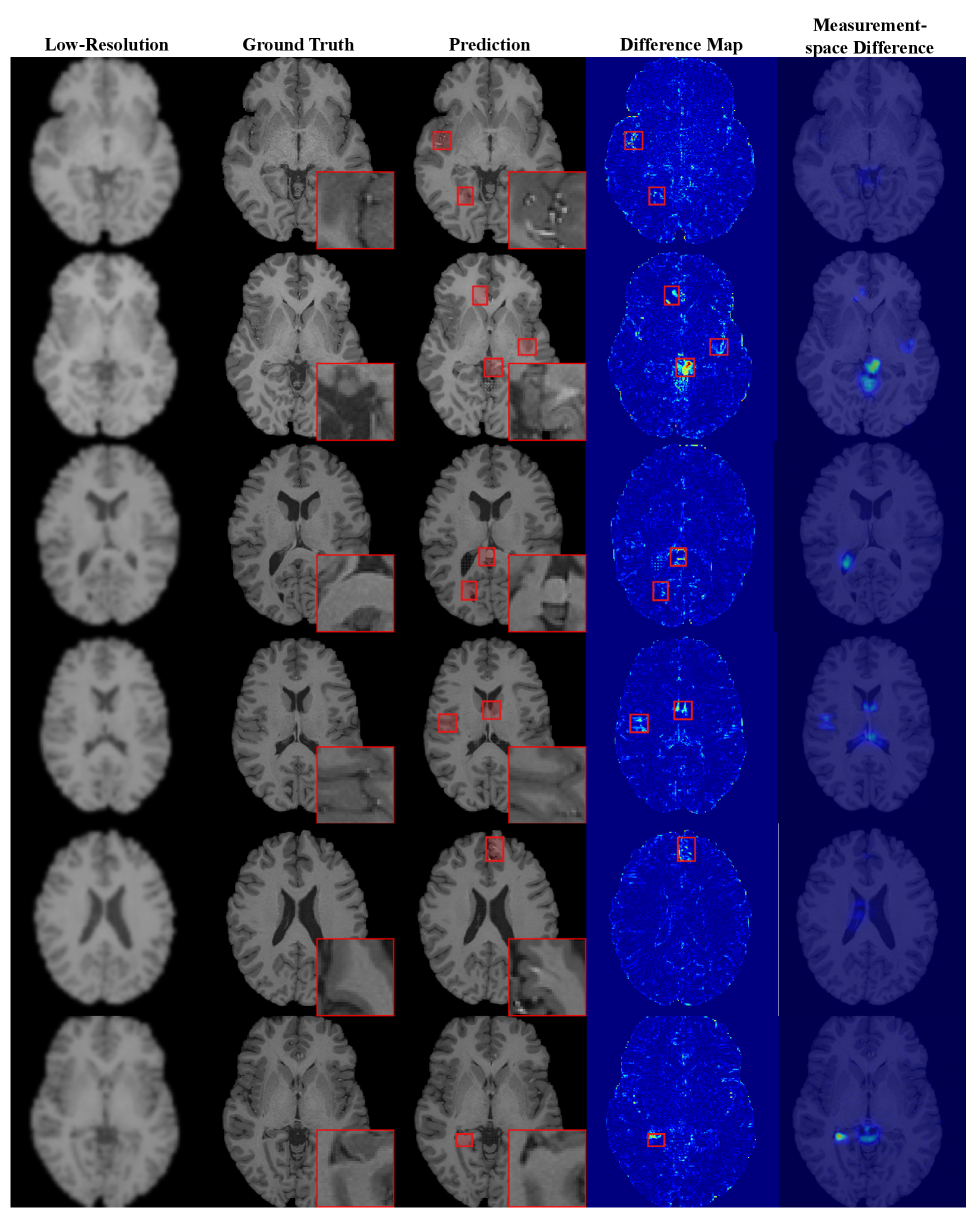

We evaluate HalluGen’s generalizability by sampling 200 images per domain-task pair (1600 total) for both intrinsic and extrinsic, summarized in Fig. 6. For MVTec AD [mvtec], semantic deviation is measured by the change in anomaly scores between ground-truth and generated images using the pre-trained PatchCore [patchcore]. On ImageNet [imagenet], it is quantified by the CLIP score, the distance between CLIP embeddings of the ground-truth and generated images.

Fig. 3 shows HalluGen generating hallucinated features on MVTec AD, such as missing transistor legs and distorted grid patterns. It maintains low FID with large change in anomaly score (Fig. 6), indicating perceptually plausible but semantically divergent outputs. HalluGen also generalizes to natural images, generating realistic distortions such as extra insect legs, warped tires with an increase in CLIP score compared to DPS (Figs. 5, 6).

Additional experiments on HCP [hcp] confirm robustness across standard restoration tasks, including super-resolution and deblurring, showing that HalluGen generalizes across both domains and restoration types.